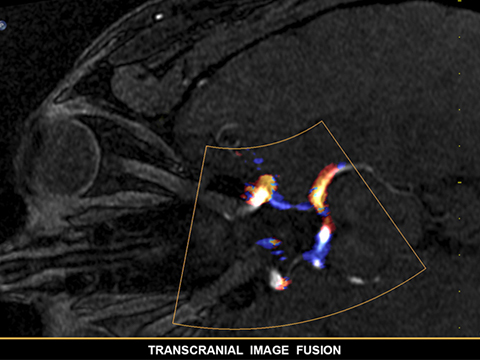

EPIQ CVxiはインターベンションエコーガイダンスの新しい方向性を示す製品です。要求の高い今日の医療課題を克服するため、多様な患者およびインターベンション手技に対応する高いレベルの臨床性能を備えています。装置上から直接、新しいEchoNavigator R3を操作することができ、ライブフュージョンイメージングの新しい合理化されたワークフローを実現します。